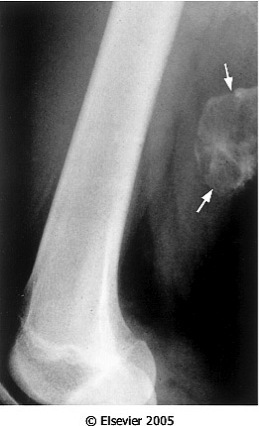

Male comes into the ER after suffering blunt trauma to his leg during a sporting event. The biopsy depicts woven bone that is well-formed at the periphery but immature bone is at the center . Xray below. Dx?

Reactive Proliferans: Myositis Ossificans